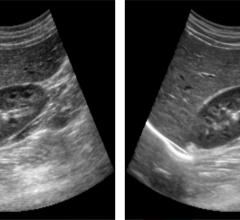

More than 50 companies and organizations will display their latest products and services at the American Society of Echocardiography’s (ASE) 26th Annual Scientific Sessions, June 12-16 at in Boston, Mass. ASE 2015 is the world’s premier meeting for cardiovascular ultrasound practitioners, and promises a wealth of cutting-edge education, research, and the latest vendor technology.